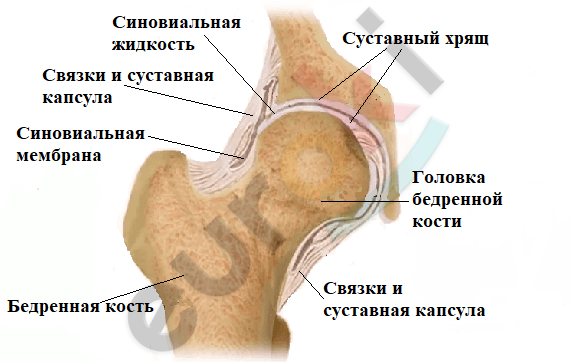

Суставная Жидкость и Головка Сустава: Обзор и Здоровье